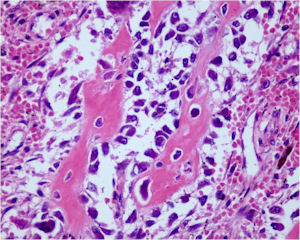

Aggressive Osteoblastoma

- Aggressive osteoblastoma is a distinct rare type of osteoblastoma that has a much more aggressive local behavior than a conventional osteoblastoma. They have a higher chance for local recurrence after removal.

- There has been controversy about the true existence of this type of tumor and whether these tumors are actually low grade osteosarcomas.

- They have a similar appearance microscopically as a conventional osteoblastoma except the osteoblasts are twice as large and have an epithelioid quality with abundant eosinophilic cytoplasm (Epithelioid Osteoblasts).

- Aggressive osteoblastoma is a borderline lesion lesion between osteoblastoma and osteosarcoma. It is not a precursor to osteosarcoma. It does not metastasize.

- Aggressive osteoblastomas usually occur in an older age group than conventional osteoblastoma.

- Most patients are older than age 30. It affects a broad variety of bones.

- Aggressive osteoblastomas are usually larger than a conventional osteoblastoma and have been reported to be up to 8.5 cm in diameter.

- Most have a similar radiographic appearance as a conventional osteoblastoma and have well defined margins, variable amounts of mineralization and peritumoral sclerosis. They occasionally have radiographic characteristics consistent with malignancy.

- Aggressive osteoblastomas are locally aggressive but never metastasize.